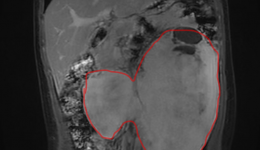

在花季年华,本应无忧无虑享受青春的小宇(化名),却遭遇了一场突如其来的健康危机,这场危机的元凶,是一个直径达20厘米的巨大腹腔肿瘤。花季少年突遭健康危机:腹腔内惊现巨大肿瘤三个月前,16岁的小宇开始出现腹胀、腹痛的症状,起初他并未在意...